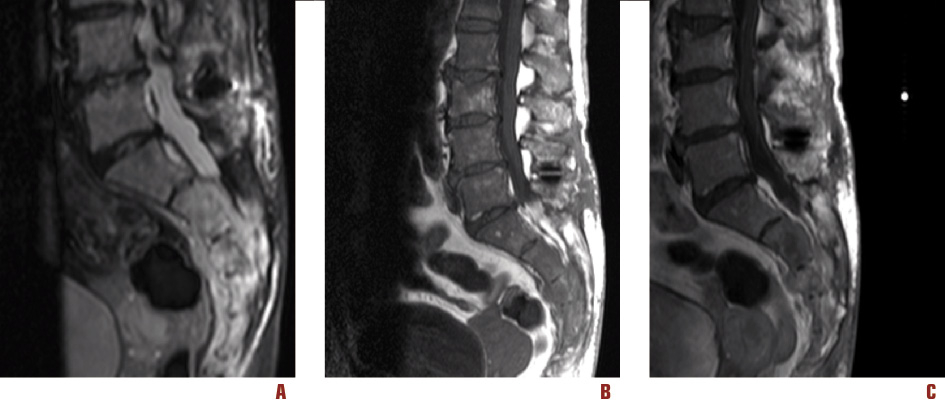

L’esame obiettivo neurologico all’ingresso mostrava un’andatura possibile solo con supporto bilaterale. La paziente presentava inoltre lieve atrofia associata a ipotonia nei distretti distali degli arti inferiori e un marcato deficit di forza negli arti inferiori (con forza residua di grado 0/5 alla flesso-estensione del piede sinistro e all’estensione dorsale del piede destro, 2/5 alla flessione plantare del piede destro, 3/5 alla flessione della coscia sul bacino a sinistra e 4/5 a destra). Vi era inoltre una marcata ipoestesia associata a disestesie urenti nella distribuzione dermatomerica L5-S1-S2 bilateralmente e un’ipoestesia distale con parestesie a tipo formicolio all’estremità degli arti superiori. I riflessi osteotendinei risultavano aboliti agli arti inferiori e ridotti (distalmente > prossimalmente) agli arti superiori. Durante la degenza presso la nostra unità la paziente veniva sottoposta a un esame elettroneurografico/elettromiografico che documentava l’assenza di risposte sensitive agli arti inferiori, l’inevocabilità di potenziali motori a carico dei nervi peroneo comune di sinistra e tibiale bilateralmente, depressione dell’ampiezza dei potenziali d’azione motoria con riduzione delle velocità di conduzione del nervo peroneo comune di destra. Veniva inoltre documentata una riduzione simmetrica dei potenziali sensitivi esplorati agli arti superiori (nervo ulnare). L’esame ad ago mostrava diffusi segni di sofferenza neurogena cronica con elementi di denervazione in atto a carico dei segmenti degli arti inferiori. Le indagini neurofisiologiche venivano integrate con potenziali evocati laser, che documentavano la non riproducibilità delle risposte corticali per stimolazione sia degli arti inferiori sia superiori. Gli esami ematochimici (routine con screening autoanticorpale e ricerca di anticorpi onconeurali) e l’esame liquorale che non evidenziava una cellularità aumentata, né atipie cellulari, risultavano negativi eccetto che per un minimo aumento dell’anti-cardiolipina IgM (33,62 MPL/ml) e dell’anti-ß2 GPI (glicosilfosfatidilinositolo) IgM (23:48 UA/ml). Si decideva pertanto di effettuare un’ulteriore valutazione di neuroimaging, documentando, mediante RM del tratto lombosacrale, la presenza di un tessuto di alterato segnale diffusamente localizzato a livello della regione sacrococcigea più evidente nelle regioni anteriori e che si estendeva ai tessuti paravertebrali e contiguo con lo spazio retrorettale (Figura 1).

Figura 1. Risonanza magnetica del tratto lombosacrale. A: sequenze STIR. B: T1 sagittale precontrasto. C: T1 sagittale postcontrasto. È evidente un’estesa alterazione morfostrutturale con presenza di tessuto di alterato segnale, maggiormente evidente nelle sequenze STIR, che presenta irregolare e disomogeneo potenziamento nelle sequenze T1 pesate dopo somministrazione ev di gadolinio, diffusamente localizzato a livello della regione sacro-coccigea con prevalente evidenza a destra e con estrinsecazione anteriore, a livello dei tessuti molli paravertebrali, in contiguità con lo spazio adiposo retrorettale

Si rendeva pertanto necessario proseguire l’iter diagnostico presso ambiente specialistico internistico-ematologico. Le Figure 1-4 mostrano le immagini della regione sacrale e del mesoretto ottenute mediante RM e TC.